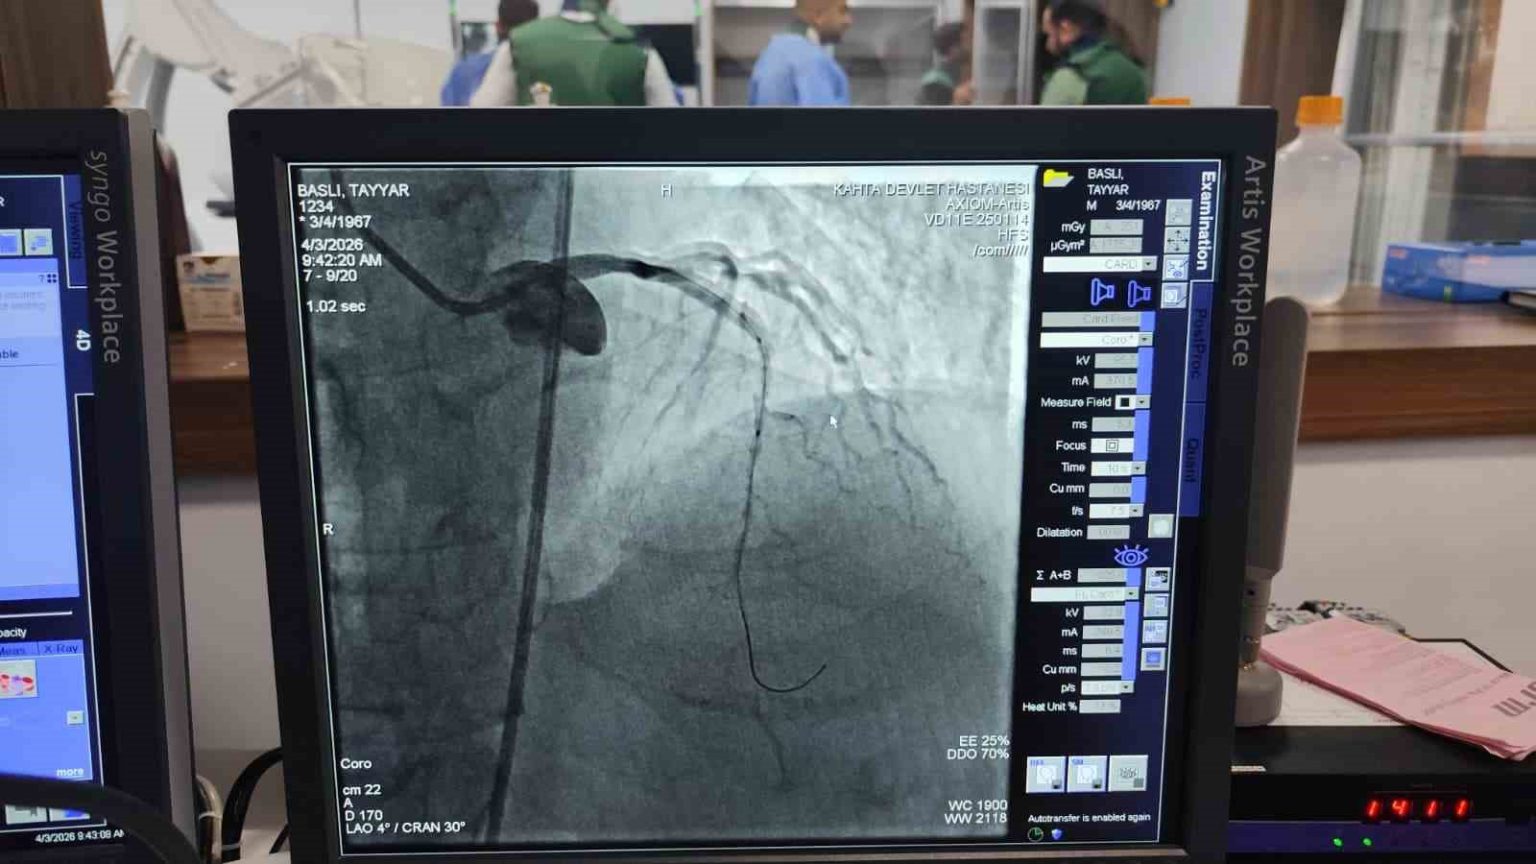

Adıyaman’ın Kâhta Devlet Hastanesi bünyesinde kurulan anjiyo ünitesinde ilk hasta da başarıyla tedavi edildi.

Kalp ve damar hastalıklarının tanı ve tedavisinde önemli bir eksikliği gidermesi hedeflenen anjiyo ünitesi, hizmete alınmasının hemen ardından ilk vakasını kabul etti. Kalp krizi şüphesiyle Kâhta Devlet Hastanesi Acil Servisi’ne başvuran hasta, yapılan ilk müdahalenin ardından vakit kaybetmeden anjiyo ünitesine alındı. Burada gerçekleştirilen operasyonla hastanın kapalı olan iki damarına stent takıldı. Müdahalenin ardından hastanın genel sağlık durumunun iyi olduğu öğrenildi.

Kâhta Devlet Hastanesi Başhekimi Dr. Mustafa Akel, “Hastanemizden 45 km mesafede ikamet eden 59 yaşındaki hastamız, göğüs ağrısı şikâyeti ile hastanemize başvurmuştur. Yapılan tetkiklerde kalp krizi geçirdiği tespit edildi ve acil bir şekilde yeni açmış olduğumuz anjio merkezimize hastayı aldık. Yapılan görüntülemede kalbinin ön damarı olan LAD mid bölgesi total tıkalı tespit edildi. Hastamızın kalbinin ön damarına iki adet stent takarak tam açıklık sağlandı. Hastamızın genel durumu iyi olup yoğun bakıma takip amacıyla alındı” dedi.

Yeni açılan anjiyo ünitesinde ilk müdahalenin başarıyla gerçekleştirilmesi, ilçede sağlık hizmetleri açısından önemli bir gelişme olarak değerlendirilirken, hastane yetkilileri acil vakalara artık ilçe içerisinde hızlı ve etkin şekilde müdahale edilebildiğini ifade etti.